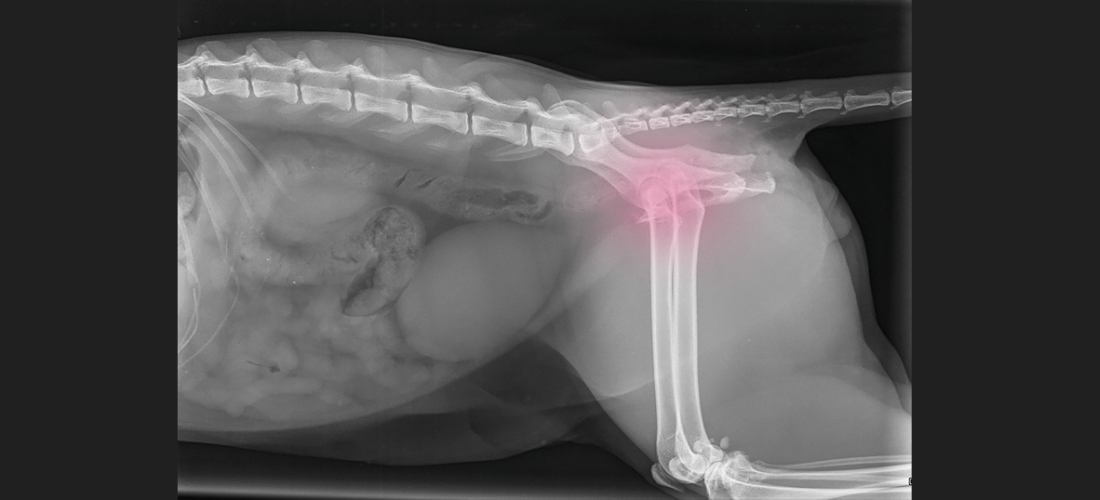

PDSA vet Ian Fleming said: “The following day, we placed Billy under a general anaesthetic to carry out X-rays to understand the full extent of his injuries, and we discovered that he had a fractured pelvis. We were also able to stitch up a nasty wound on his back leg.

“Billy’s injuries were consistent with a road traffic accident. He needed pain relief and around-the-clock care, so he was hospitalised for another three nights. He also initially struggled to pee properly due to the severity of his injuries, so we couldn’t send him home until we were confident that he could pass urine comfortably.”